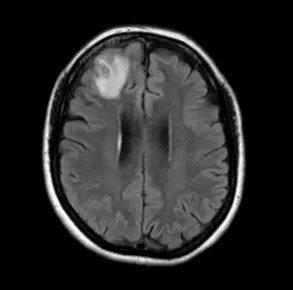

하지만 증상은 더 심해졌고, A 씨는 발에서 시작해 다리까지 타는 듯한 느낌을 받기 시작했다. 결국 병원에 갔지만 아무런 진단을 받지 못했다. 하지만 온몸이 타는 듯한 통증과 더불어 심한 두통까지 앓게 됐고 그는 기생충 감염 진단을 받게 됐다.

A 씨의 진단명은 광동주혈선충증이었다. ‘쥐 폐선충’으로도 알려진 이 감염병은 광동주혈선충의 중간숙주(조개 등의 담수산 패류와 민달팽이)나 운반숙주(새우, 게, 개구리 등)를 덜 익혀 먹을 경우 감염된다. 때로는 유충으로 오염된 채소를 섭취하거나 물을 마시는 경우에도 감염될 수 있다.

쥐 폐선충의 초기 증상은 구역, 구토, 복통 등이며 두통, 발열, 근육 통증, 피로, 불면증 및 신경학적 증상이 나타날 수 있다. 목 경직과 통증, 피부의 따끔거림이나 타는 느낌, 복시, 배뇨 또는 배변 어려움, 발작 등이 동반될 수 있다. 어린이의 경우 발열, 무기력, 위장 통증, 근육 경련, 경련 및 사지 약화 등의 증상이 나타날 수 있어 주의해야 한다.